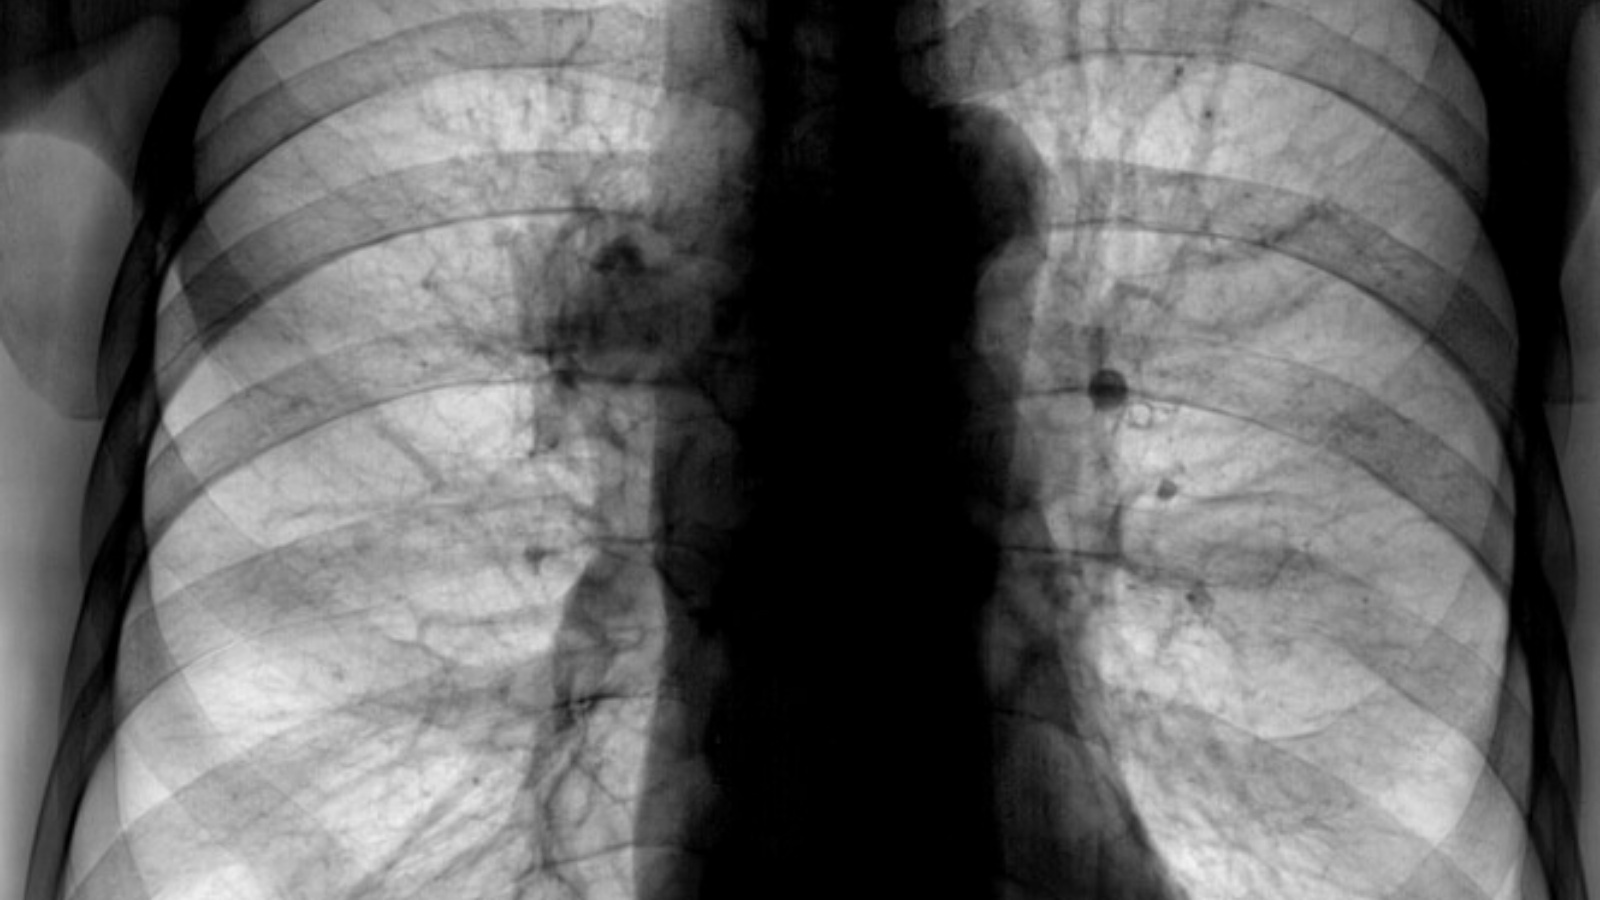

«Часто болеют курильщики со стажем из-за своей вредной привычки. Потому что выжигают свои легкие и создают благоприятную среду для размножения бактерий», — пояснила специалист.

Также она отметила, что снятие диагноза ХОБЛ возможно даже при сохранении 30% легких. Но, только в случае отказа от курения, использования ингалятора и исполнения рекомендаций специалиста. В лечебной практике Алины Бурчагиной были случаи возвращения функции внешнего дыхания до 70-80%.

ХОБЛ помолодел, если раньше этот диагноз ставили пациентам в 50+ лет, то теперь «любители» покурить в возрасте 40+, пристрастившиеся к сигаретам с 14-15 лет, имеют легочную недостаточность.